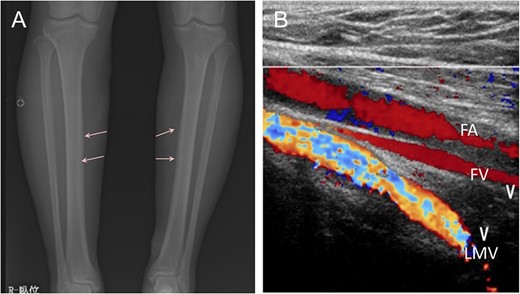

Radiograph showed bone cortex hypertrophy (arrow) of the lower limbs (A). Dilation of superficial vein in bilateral lower limbs, retrograde flow of bilateral great saphenous vein and persistence of the lateral marginal vein were detected by ultrasonography. FA, femoral artery; FV, femoral vein; LMV, lateral marginal vein (B).